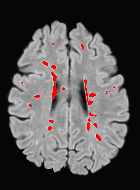

Patch size is another important parameter of the network. In computer vision applications such as object detection, usually a whole 2D image is used as a feature. However, full 3D medical images can not typically be used because of memory limitations. Fig. 4 shows examples of lesion memberships obtained with different sized 2D patches. As the patch sizes increases, the false positives that are mostly observed in the cortex tend to decrease. Fig. 5 shows a plot of Dice and LFPR with various patch sizes, ordered from left to right according to their increasing size. Note that smaller patches ( to ) produced significantly lower Dice and higher LFPR compared to other patches (), as seen from the memberships in Fig. 4. Also some of the highest Dice and lowest LFPR were observed for patches with large in-plane size, i.e., , , and . It was observed in Fig. 5 that there is no significant difference between Dice coefficients for , , or , but LFPR of both and are significantly lower than that of (). We chose as the optimal patch size. Other choices of smaller and patches (not shown) yielded worse results. Note that although training was performed with different patch sizes, the memberships were generated slice by slice, as the trained model consisted only of convolutions and did not need any information about patch sizes.